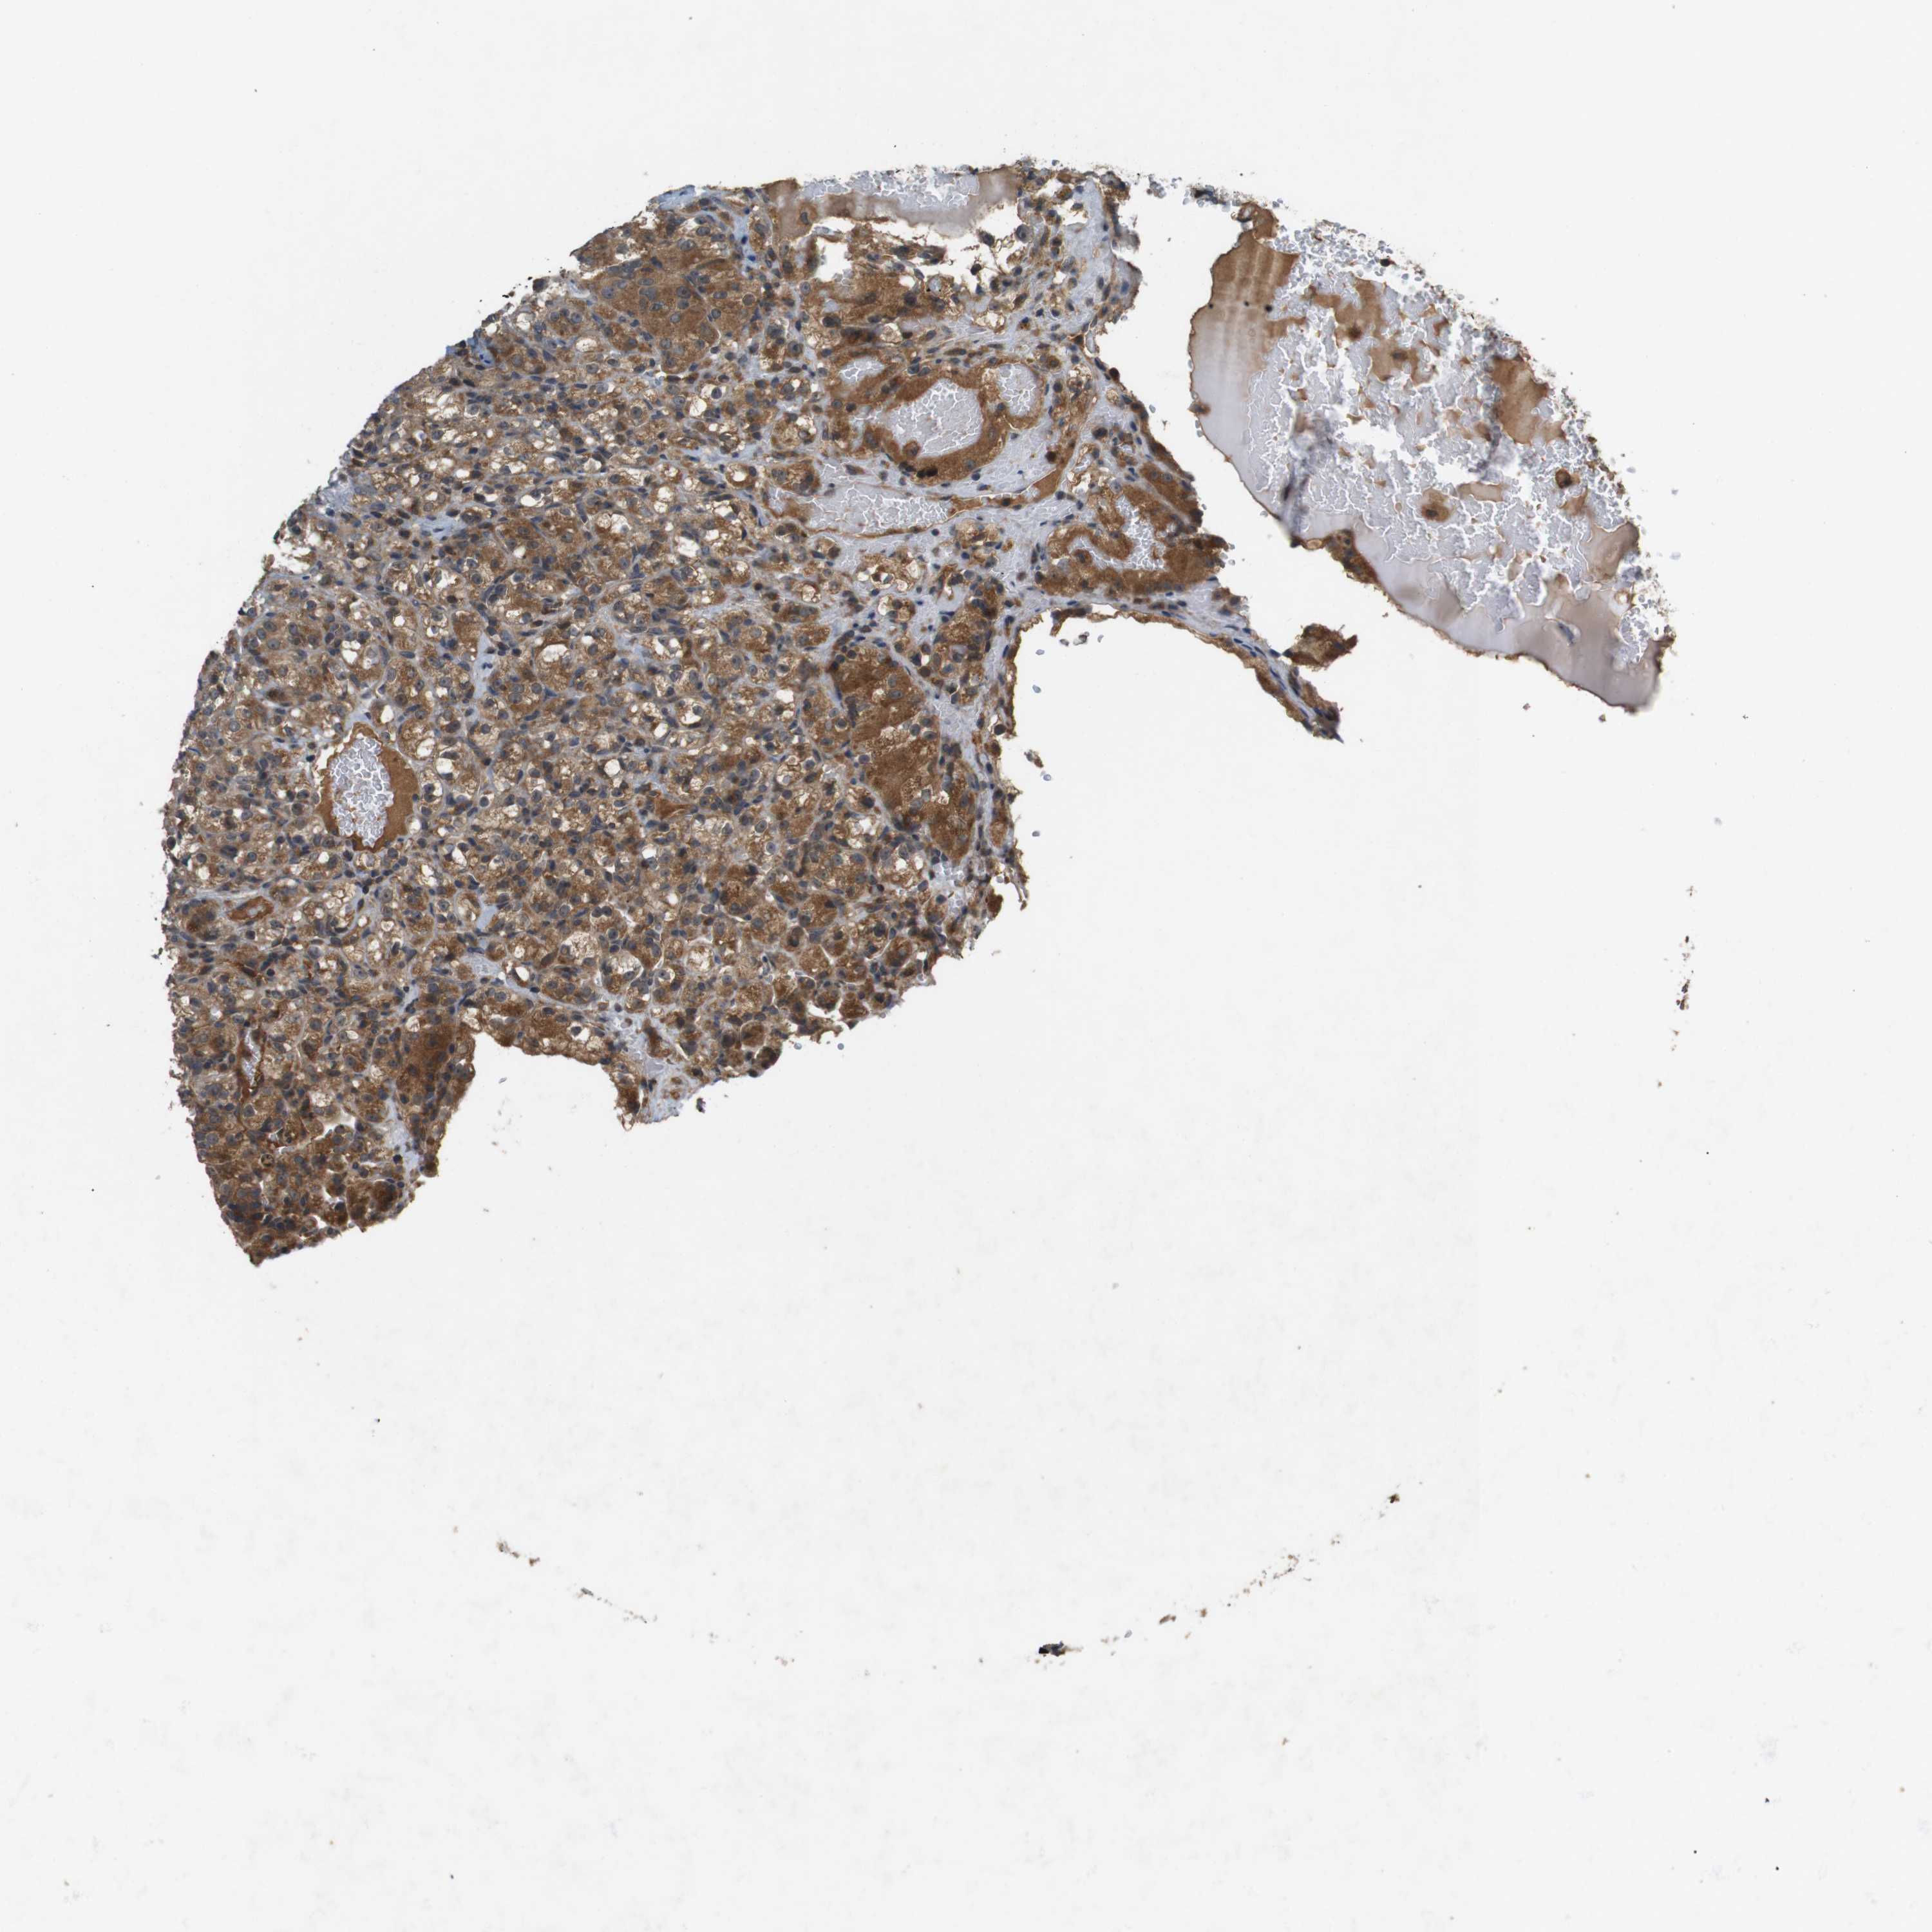

KIDNEY RENAL CLEAR CELL CARCINOMA (TCGA) - Interactive survival scatter ploti

The Survival Scatter plot shows the clinical status (i.e. dead or alive) for all individuals in the patient cohort, based on the same data that underlies the corresponding Kaplan-Meier plots. Patients that are alive at last time for follow-up are shown in blue and patients who have died during the study are shown in red.

The x-axis shows the expression levels (FPKM) of the investigated gene in the tumor tissue at the time of diagnosis. The y-axis shows the follow-up time after diagnosis (years). Both axes are complimented with kernel density curves demonstrating the data density over the axes. The top density plot shows the expression levels (FPKM) distribution among dead (red) and alive patients (blue). The right density plot shows the data density of the survived years of dead patients with high and low expression levels respectively, stratified using the cutoff indicated by the vertical dashed line through the Survival Scatter plot. This cutoff is automatically defined based on the FPKM cutoff that minimizes the p-score. The cutoff can be changed by dragging the vertical line or by entering a cutoff value in the square labeled "Current cut-off".

Under the Survival Scatter plot the p-score landscape (black curve; left axis) is shown together with dead median separation (red curve; right axis). Dead median separation is the difference in median mRNA expression between patients who have died with high and low expression, respectively. It is calculated as follows: median FPKM expression of dead patients with high expression - median FPKM expression of dead patients with low expression. This is intended to aid the user in visually exploring custom cutoffs and the associated p-scores and dead median separation.

Individual patient data is displayed and can be filtered by clicking on one or more of the category buttons on the top of the page. Categories describing expression level and patient information include: high, low, alive, dead, female, male and tumor stages. The scale of the x-axis can be toggled between linear and log-scale by clicking on the "x log" button. Mouse-over function shows TCGA ID, patient information and mRNA expression (FPKM) for each patient.

& Survival analysisi

Kaplan-Meier plots summarize results from analysis of correlation between mRNA expression level and patient survival. Patients were divided based on level of expression into one of the two groups "low" (under cut off) or "high" (over cut off). X-axis shows time for survival (years) and y-axis shows the probability of survival, where 1.0 corresponds to 100 percent.

NFKBIE is not prognostic in Kidney Renal Clear Cell Carcinoma (TCGA)

Best expression cut offi

Based on the FPKM value of each gene, patients were classified into two groups and association between prognosis (survival) and gene expression (FPKM) was examined. The best expression cut-off refers the FPKM value that yields maximal difference with regard to survival between the two groups at the lowest log-rank P-value. Best expression cut-off was selected based on survival analysis .

When clicking on this number, the vertical dashed line indicating cut-off, the interactive survival plot, and the Kaplan-Meier curve will be adjusted to show results based on the best expression cut-off.

: 29.79

P scorei

Log-rank P value for Kaplan-Meier plot showing results from analysis of correlation between mRNA expression level and patient survival.

N/A

TCGA RNA samplesi

RNA-seq data is reported as average FPKM (number Fragments Per Kilobase of exon per Million reads), generated by the The Cancer Genome Atlas (TCGA) .

Normal distribution across the dataset is visualized with box plots, shown as median and 25th and 75th percentiles. Points are displayed as outliers if they are above or below 1.5 times the interquartile range. FPKM values of the individual samples are presented next to the box plot.

Average pTPM 34.6

Number of samples 521